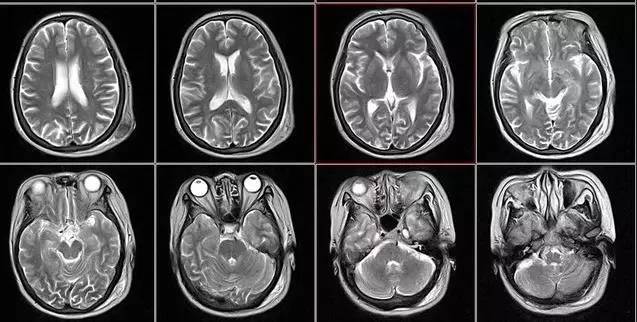

X光:像把面包压扁了看 X光会穿过人体,遇到被遮挡的部位,底片上不会曝光,洗片后这个部位就是白色的。 就像一片面包或一块棉花,看不到里面的纤维纹理,但用手压瘪了会清晰一些。X光最大缺点是受制于深浅组织的影像相互重叠和隐藏,有时需要多次多角度拍摄X光片。 CT:像把面包切片看 CT的检查原理是X光会分层穿过人体,之后通过电脑计算后二次成像,就像把一片面包切成片来看。优点是可以分层看,经计算后可以显示出更多的组织信息。 B超:像挑西瓜前敲一敲 B超的原理是用超声波穿透人体,当声波遇到人体组织时会产生反射波,通过计算反射波成像。就像挑西瓜一样,边敲边看显示病灶情况 核磁共振机使用较强大的磁场,使人体中所有水分子磁场的磁力线方向一致,这时磁共振机的磁场突然消失,身体中水分子的磁力线方向,突然恢复到原来随意排列的状态。简单说就相当于用手摇一摇,让水分子振动起来,再平静下来,感受一下里面的振动。所以,核磁共振(MRI)也被戏说为是摇摇看的检查。 就诊时,医生常会开各种各样的影像学检查单:超声、CT、核磁……不少患者会质疑医生故意开高价检查单。其实,医生是依据不同病情选不同影像检查的。 1、外伤骨头——粗看X光片、细看CT 各种外伤,如果怀疑伤到了骨头,优先选择X光照片,检查结果快速易得。若要进一步观察,可以选择CT。超声、核磁对于骨皮髓质等看不大清,一般不选择。 2、颈椎腰椎——最佳选核磁、次选CT 颈椎病、腰椎间盘突出等椎间盘疾病需要观察椎间盘与相应的神经根,要想更好观察这些软组织,最优选择就是核磁。同样,对于关节、肌肉、脂肪组织检查,核磁也是首选。 3、胸部——粗看X光片,细看CT X光胸片可粗略检查心脏、主动脉、肺、胸膜、肋骨等,可以检查有无肺纹理增多、肺部钙化点、主动脉结钙化等。 胸部CT检查显示出的结构更清晰,对胸部病变检出敏感性和显示病变的准确性均优于常规X光胸片,特别是对于早期肺癌确诊有决定性意义。但是CT检查的辐射剂量高于X光。核磁对于肺部疾病的诊断,应用非常有限。 4、腹部盆腔——除肠道外,一般超声都能查 腹腔器官受呼吸影响较大,进而影响到CT、核磁成像,而超声不会因此受影响。同时,超声对肝脏、脾脏、胰腺、肾脏、盆腔脏器等诊断准确率较高。 但是超声受气体干扰很大,对于肠道等含气较多的器官,超声诊断准确率会降低。 5、心脏——排除冠心病用CT,看心功能用超声 常规的心脏结构与功能检查,心脏彩超所提供的信息已经较为充分,又简单易行。